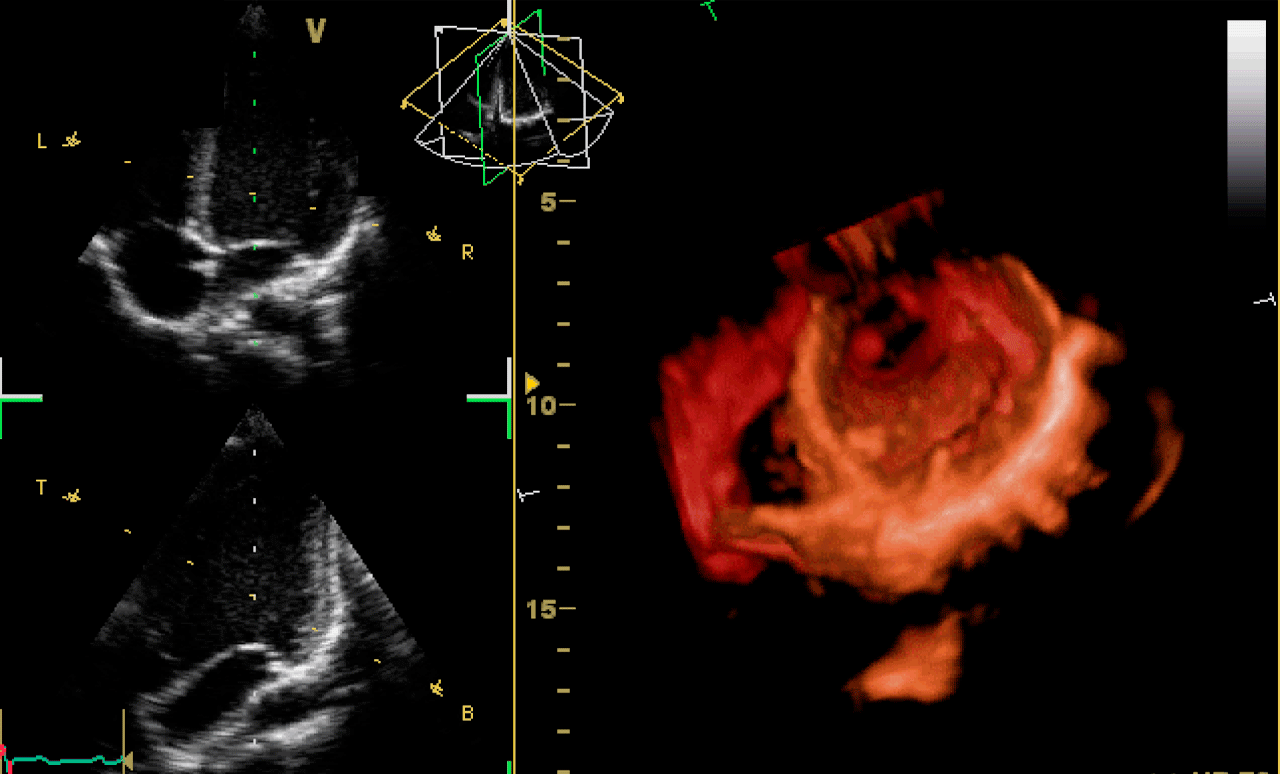

3D- и 4D-эхокардиография

3D-эхоКГ фиксирует объёмное изображение. Он не комбинирует плоские срезы, как обычное УЗИ, а собирает пространственную модель. Получается 3D-реконструкция камер, клапанов и перегородок сердца, где можно рассмотреть структуру под любым углом. 4D-визуализация — трёхмерная эхоКГ, которая показывает движения органа в реальном времени.

Такие исследования стоят дороже, и аппараты есть не во всех клиниках, особенно в регионах. 3D и 4D УЗИ применяются, когда нужна объёмная и точная визуализация:

-

при сложных врождённых пороках у детей;

для тщательного исследования митрального и аортального клапанов;

при малоинвазивных операциях, в том числе в процессе проведения;

для динамического мониторинга после пластики либо протезирования клапанов.